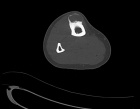

21 year old male with increasing leg pain and enlarging mass for three years

Zoom image: Radiological image Radiological image.